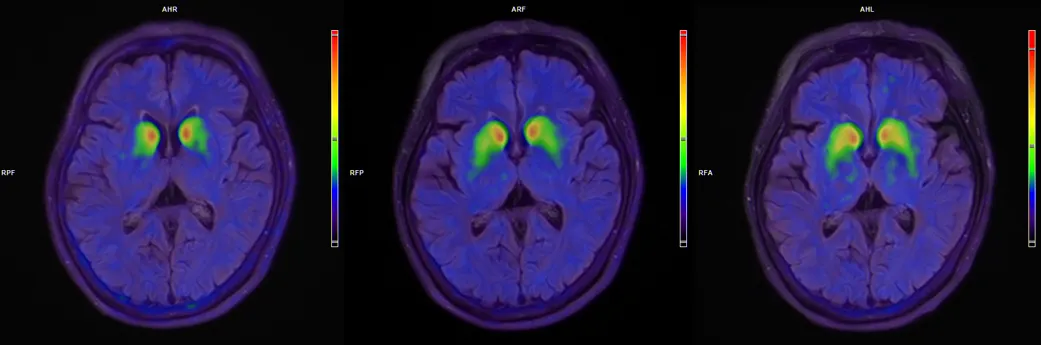

· 18F-FP-CIT PET影像学显示,双侧壳核移植区多巴胺转运体信号持续增强,为细胞存活和功能整合提供客观证据。

患者脑部术前、3个月、6个月的18F-FP-CIT PET图像